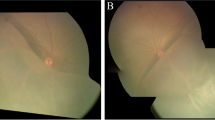

Patient II (aged 40 years), had bilateral retinoschisis. He had diminution of vision in both the eyes since the age of 7. On a recent examination, his best corrected visual acuity was 3/60 with a refractive error of +9.00DS/−1.25DC*90 and +4.50DS/−2.00DC*90 in the right eye and left eye respectively. The right eye had large inner layer breaks, but no retinal detachment. The left eye developed rhegmatogenous retinal detachment due to outer retinal break and hence was subjected to surgery. After the sclerotomies are made for vitreoretinal surgery, attempt was made to collect uncontaminated schitic fluid. A needle connected to a syringe was passed across the vitreous cavity into the schitic cavity through a pre-existing inner retinal layer break or by penetrating the inner layers if no breaks existed. Once the needle tip was positioned within the schitic cavity, gentle aspiration of the schisis fluid was done under direct visualization using a 2 ml syringe until the schitic cavity collapsed. Throughout this procedure, care was taken not to suck the vitreous gel and the infusion was shut off to avoid dilution. Once the needle was withdrawn the intraocular pressure was restored with balanced salt solution infusion and surgery proceeded with. Representative OCT images and ERG readings of patient II are shown in Fig. 2.

Representative optical coherence tomography (OCT) images and electroretinogram (ERG) readings of patient II. a Preoperative OCT image of the left eye with corresponding fundus picture, suggestive of detached macula (yellow arrow) and schisis (red arrow). b Postoperative OCT image of the left eye showing attached macula (yellow arrow) and partly collapsed schisis (red arrow). c ERG of the right and left eye showing grossly delayed and reduced single flash rod responses and negative waveform in combined responses